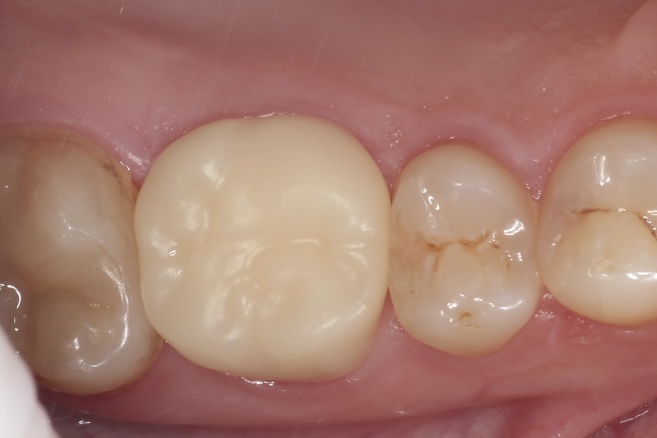

Наши работы